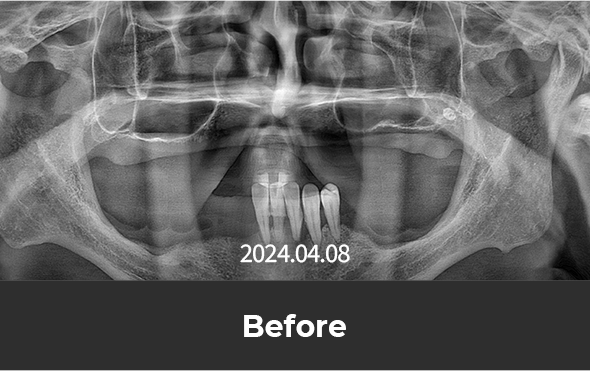

치료 후 사진

[ 환자분의 동의서 작성 후 게시하였습니다 ]